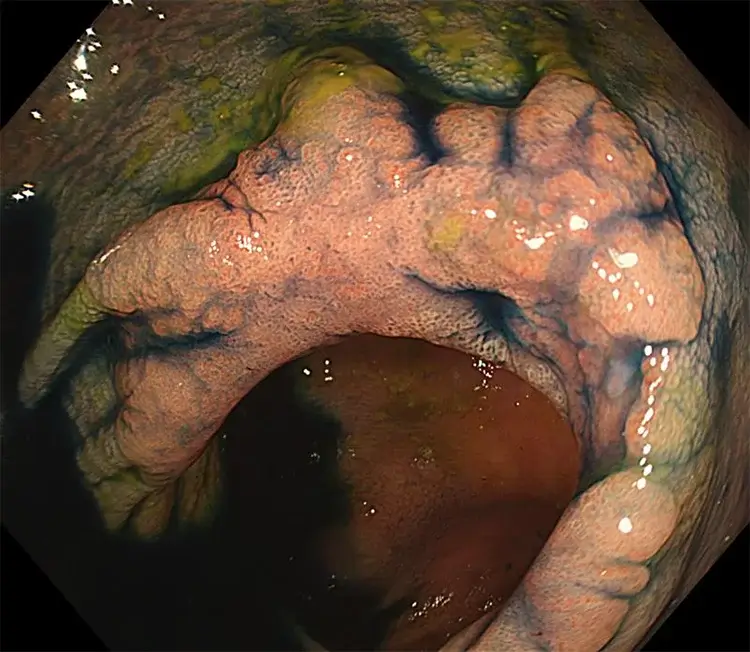

Endoscopic Submucosal Dissection (ESD)

- Endoscopic Submucosal Dissection (ESD) is performed during colonoscopy. It is a procedure used to remove larger or more complex polyps from the bowel lining. A special knife is used to carefully separate it from the deeper layers of the bowel wall. Unlike other methods, the polyp is removed in one piece, which allows precise analysis in the laboratory and reduces the risk of it coming back.

- Rectal polyps: ESD is particularly important for rectal polyps, as these types of polyps carry a higher risk of developing bowel cancer. By enabling precise, one-piece removal of complex or early cancerous polyps, ESD provides accurate diagnosis and complete treatment for early cancers, while often avoiding the need for major surgery.